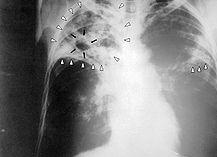

Tuberculosis. La tuberculosis (abreviada TBC o TB), llamada antiguamente tisis (del griego φθίσις a través del latín phthisis), es una enfermedad infecciosa, prevenible y curable que se transmite por el aire, al igual que el resfriado común. Afecta, por lo general, a los pulmones y compromete otras partes del cuerpo, como el cerebro, los riñones o la columna vertebral. Causada por diversas especies del género Mycobacterium, todas ellas pertenecientes al Complejo Mycobacterium tuberculosis.

Aunque la tuberculosis es una enfermedad predominantemente de los pulmones, puede también verse afectando el sistema nervioso central, el sistema linfático, circulatorio, genitourinario, gastrointestinal, los huesos, articulaciones y aun la piel. Los signos y síntomas más frecuentes de la tuberculosis son: tos con flema por más de 15 días, a veces con sangre en el esputo, fiebre, sudoración nocturna, mareos momentáneos, escalofríos y pérdida de peso. Si la infección afecta a otros órganos por volverse sistémica, aparecen otros síntomas.

Diagnóstico

La TBC activa se diagnostica por la detección de Mycobacterium tuberculosis en cualquier muestra del tracto respiratorio (TBC pulmonar) o fuera de él (TBC extrapulmonar). Aunque algunos métodos más modernos (diagnóstico molecular) han sido desarrollados, la visión microscópica de bacilos ácido-alcohol resistentes (BAAR) y el cultivo en medio Löwenstein-Jensen siguen siendo el gold standar del diagnóstico de la TBC., especialmente en países con bajos recursos sanitarios.